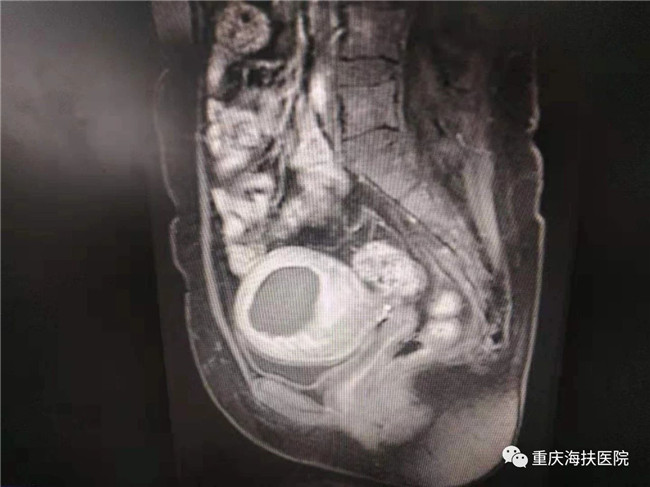

李女士因為有保留子宮和再生育的愿望,毅然選擇了不開刀、不流血的聚焦超聲消融手術,術中消融病灶達6公分,消融效果良好。術后李女士發現自己的痛經癥狀明顯緩解,并在1年后成功妊娠,于2019年9月18日剖宮產一個6.2斤的海扶小公主!